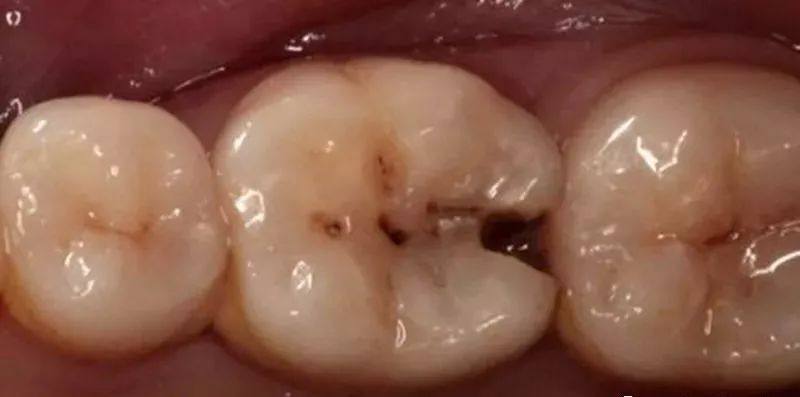

塞牙易令你患齲齒。好多塞牙狀況,都是會導致齲齒的。

1、鄰面的齲齒破壞了正常的牙齒結構,引致縫隙嘅出現。

1.對於因兩粒牙之間嘅縫隙引起食物嵌塞嘅患者,若有鄰面的齲齒要根據具體情況選擇相應嘅填補或修復方法,恢復正常嘅接觸關係。